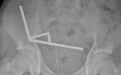

带刀生活

一位44岁的坦桑尼亚男子成了今年最令医生震惊的狠人:他胸腔里插着一把刀生活了8年,自己竟然浑然不觉[2]。

一把刀几乎贯穿了患者的右侧胸腔,并从他的肺叶中间穿过,但他竟然在8年间对此浑然不觉。| Kivuyo et al.

直到这位患者因为伤口流脓前来就医,医生才通过X光检查发现了这个惊人的秘密。检查显示,从把手上脱落的金属刀刃几乎贯穿了患者的胸腔。在手术取出刀片、清除坏死组织之后,男子顺利痊愈。

患者8年前曾卷入一场暴力冲突,刀子就在那时进入了他的身体。人体内的异物周围常会形成纤维囊包裹,可能正是这种包裹限制了炎症与组织损伤,让患者没有察觉刀的存在。

医生强调,刀片滞留和当地医疗资源的匮乏密切相关。如果患者受伤时能进行全面检查,就不会留下这种隐患。